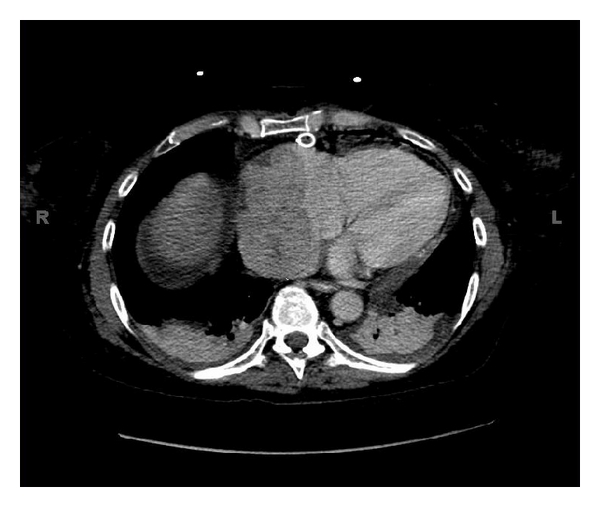

Thirteen years after the allograft, she complained of shortness of breath and dyspnea on exertion. She denied any chest pain and any palpitations. The patient was put on albuterol, but continued to have shortness of breath. An echocardiogram in her family physician’s office indicated the presence of a “large right atrial thrombus”, and she was immediately referred to the hospital emergency department. A venous ultrasound of the right and left lower extremities showed no evidence of venous thrombosis. Imaging studies ruled out pneumothorax and/or pulmonary embolism. Echocardiogram documented a normal ejection fraction (60–65%); however, a mass measuring 6.7 × 3.3 cm was seen in the right atrium encroaching the right atrial wall and a large pericardial effusion with tamponade. CT confirmed a large right cardiac atrial mass, extending into the inferior vena cava and also involving the superior vena cava as it enters the atrium and the pericardial effusion (Figure 1). The patient then underwent a pericardial window to drain the pericardial effusion. The effusion cytology showed that 50% of the cells were plasma cells, which was confirmed by immunoperoxidase CD138 positive staining. In situ hybridization stains for kappa and lambda chains indicated that almost all of the plasma cells were positive for lambda light chains. The diagnosis of monoclonal plasmacytosis was made. Biopsy of the pericardial tissue ruled out other malignancies, amyloidosis, and vasculitis.